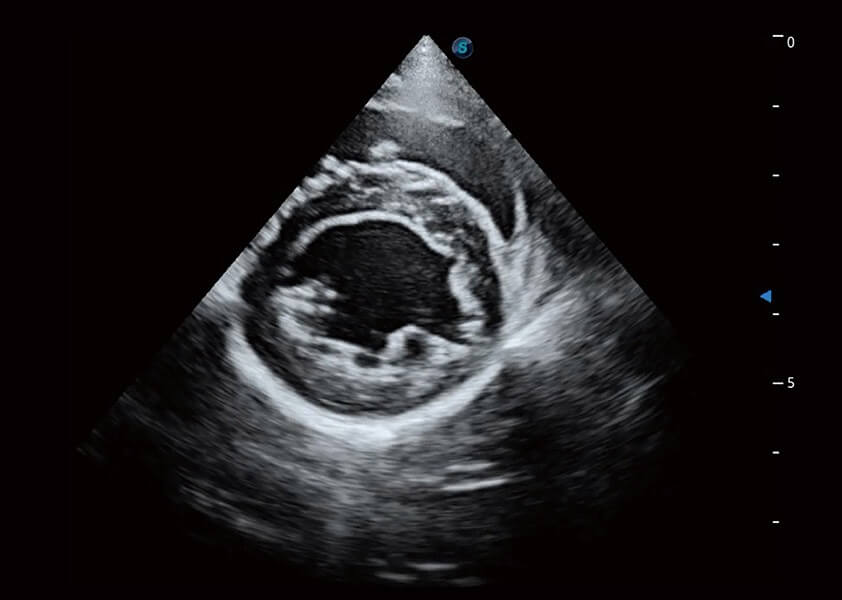

ProPet 60 作为一款高端台式动物超声设备,为动物医生的日常诊断提供了一系列贴合动物临床需求、解决临床实际问题的高级成像功能。凭借全系列高清探头,满足医生对腹部、心脏、生殖、浅表、肌骨等成像的所有需求,切实帮助您提升检查效率,提高诊断信心。

动物是人类最亲密的朋友和最值得信赖的伙伴。米兰官方网站也一直致力于探索动物专用的超声影像解决方案。 全新推出的ProPet系列,是米兰官方网站在动物超声影像智能化、专业化、精准化的一次跨越式革新。动物不能用言语来表述自己的不适,通过超声影像,ProPet系列搭建了动物医生与不同物种沟通的“桥梁”,为动物医生注入了“治愈之力”。